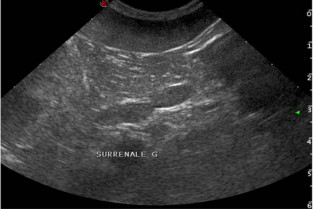

- reconnaître et d’identifier les lésions échographiques spléniques, ganglionnaires et surrénaliennes ;